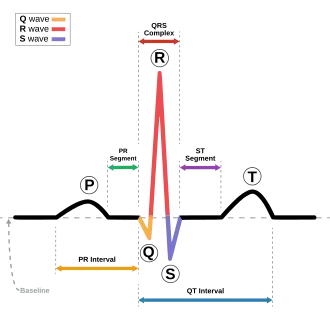

| This condition affects the QT interval (in blue). | |

Andersen–Tawil syndrome affects the heart by prolonging the QT interval, a measure of how long it takes the heart to relax after each heart beat. This, as in other forms of long QT syndrome, can lead to abnormal heart rhythms such as ventricular ectopy or ventricular tachycardia causing palpitations.[6] The ventricular tachycardia seen in Andersen–Tawil syndrome often takes a form known as bidirectional ventricular tachycardia. The arrhythmias seen in association with the condition can cause sudden cardiac death, but the risk of this is lower than in other forms of long QT syndrome.[1] The physical abnormalities associated with Andersen–Tawil syndrome typically affect the head, face, limbs and spine. Abnormalities of the head and face include an unusually small lower jaw (micrognathia), low-set ears, widely spaced eyes (hypertelorism), a broad forehead and nasal root, a high arched or cleft palate, and a long narrow head (scaphocephaly).[4] Abnormalities of the limbs and spine include an abnormal curvature of the fingers, particularly the fifth finger (clinodactyly), fused fingers or toes (syndactyly), short stature, and a curved spine (scoliosis).[4]

Andersen–Tawil syndrome increases the risk of abnormal heart rhythms by disturbing the electrical signals that are used to coordinate individual heart cells. The genetic mutation disturbs an ion channel responsible for the flow of potassium, reducing the /K1 current. This prolongs of the cardiac action potential – the characteristic pattern of voltage changes across the cell membrane that occur with each heart beat, and depolarises the resting membrane potential of cardiac and skeletal muscle cells.[4]

Cardiac and skeletal muscle cells, when relaxed, have fewer positively charged ions on the inner side of their cell membrane than on the outer side, referred to as their membranes being polarised.[8] The main ion current responsible for maintaining this polarity is /K1, and a decrease in this current leads to less polarity at rest, or a depolarised resting membrane potential. When these cells contract, positively charged ions such as sodium and calcium enter the cell through ion channels, depolarising or reversing this polarity. After a contraction has taken place, the cell restores its polarity (or repolarises) by allowing positively charged ions such as potassium to leave the cell, restoring the membrane to its relaxed, polarised state.[8] The genetic mutation found in those with Andersen–Tawil decreases the flow of potassium, slowing the rate of repolarisation which can be seen in individual cardiac muscle cells as a longer action potential and on the surface ECG as a prolonged QT interval.[4]